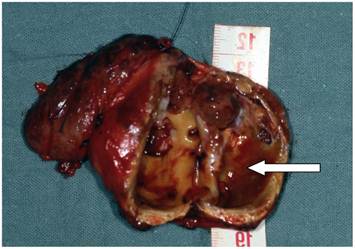

Figure 2

Cystic mass (arrow) (5,5 x 3,5 x 3,5 cm) against the right thyroid lobe

However, the only feature that may permit the preoperative diagnosis of parathyroid cancer is clear evidence of invasion into adjacent tissue. Tomography was performed in one patient and demonstrated a cystic mass at the inferior aspect of the thyroid lobe (Fig 1).

Enhanced neck computed tomography showing a cystic mass (arrow) at the inferior aspect of the right thyroid lobe with a tracheal compression.